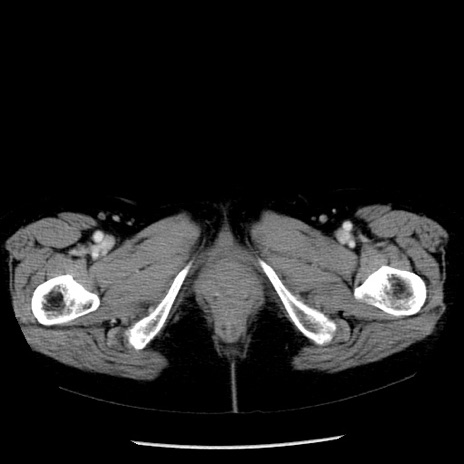

症例13(横断像)

【症例】70歳代女性

【主訴】腹痛、嘔吐

【現病歴】15時間程前(昨晩)より腹痛あり。今朝になっても症状の改善なく、嘔吐あり。腹痛も増悪あり、救急外来受診。

【既往歴】子宮癌全摘術後

【身体所見】意識清明、BP 121/72mmHg、P 74bpm、SpO2 100%(RA)、腹部:平坦・軟、腸雑音ほぼ聴取せず。下腹部・心窩部・臍左上に圧痛あり。反跳痛なし。

【データ】WBC 10600、CRP 0.15